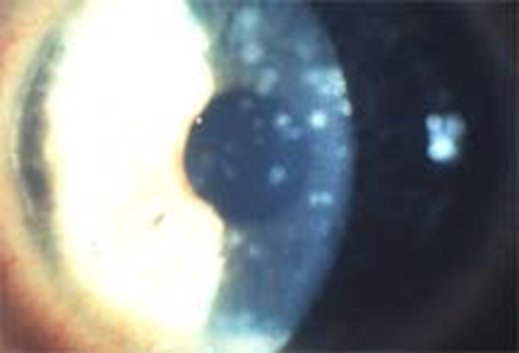

Hình ảnh viêm giác mạc đốm |

Hình ảnh viêm giác mạc đốm

Những trường hợp nặng có thể gây tổn thương giác mạc như viêm giác mạc chấm nông, viêm giác mạc đốm làm cho giác mạc bị mờ đục, khi đó thị lực giảm nhiều và kéo dài dai dẳng hàng tháng. Nếu nguyên nhân là Adenovirus thì người bệnh có thể bị sốt nhẹ, chảy nước mũi, có sưng hạch trước tai hoặc hạch góc hàm, viêm họng, amidan sưng viêm.